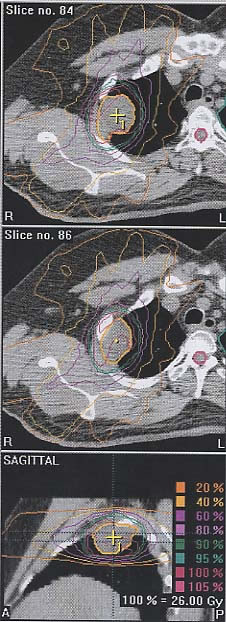

Thymuskarzinom: Bestrahlungsplan

Bestrahlungspläne